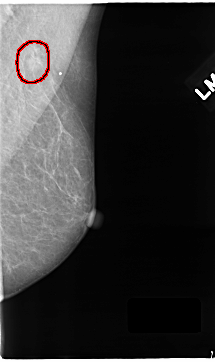

C_0122_1.LEFT_MLO

LEFT_MLO LINES 4704 PIXELS_PER_LINE 2792 BITS_PER_PIXEL 12 RESOLUTION 50 OVERLAY

FILE: C_0122_1.LEFT_MLO.OVERLAY

TOTAL_ABNORMALITIES 1

ABNORMALITY 1

LESION_TYPE MASS SHAPE OVAL MARGINS SPICULATED

ASSESSMENT 4

SUBTLETY 4

PATHOLOGY MALIGNANT

TOTAL_OUTLINES 1

BOUNDARY